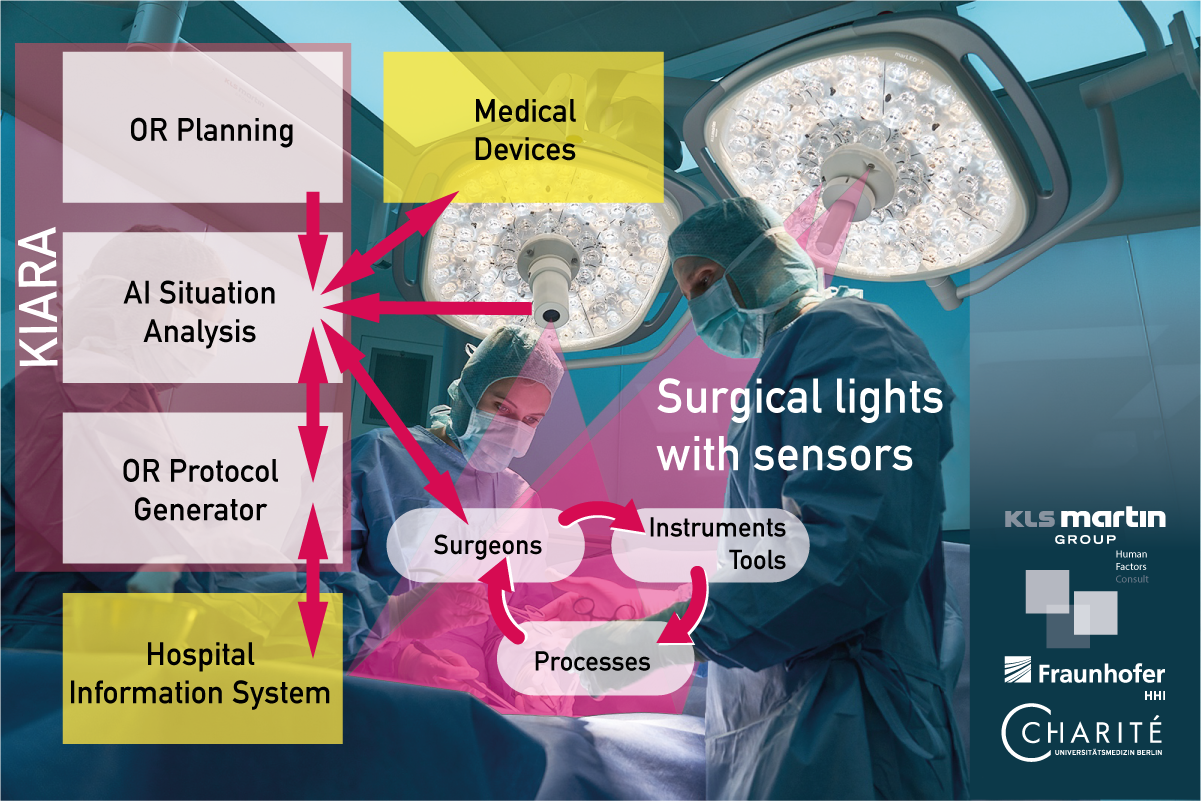

KIARA – AI-based recording of work processes in the operating room for automated generation of the OR report

The operative report (surgery report) is a vital document that captures essential details of surgical interventions, including the type, course, achieved goals, and any encountered challenges. It serves the comprehensible transmission of information to medically knowledgeable third parties such as the attending medical staff and thus ensures therapy safety, accountability and proof of service provision for billing. However, creating a complete and accurate operative report demands considerable time from surgeons, taking them away from patient care. To address this challenge and optimize clinical processes, the KIARA system (KI-basierte Erfassung von Arbeitsprozessen im Operationssaal zur automatisierten Erstellung des OPBerichts / AI-based recording of work processes in the operating room for automated generation of the OR report) proposes an AI-based interactive approach for automatic documentation, reducing paperwork while enhancing medical, organizational, and administrative efficiencies. The time freed up can be used by surgeons to treat patients.

The underlying AI for situation recognition in a robust documentation system is a necessary and essential first step for the automation and optimization of further clinical processes. The KIARA system aims to assist here and significantly simplify the process by collecting as much report-relevant information as possible from the operating room via sensors installed in OR lamps and distributed in the room, evaluating it, and compiling it into a report that only needs to be checked and approved.